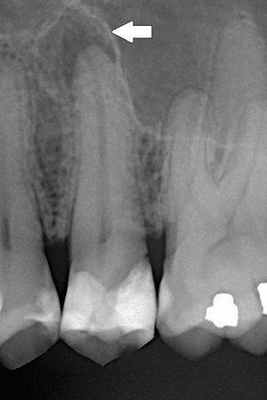

Рентгенологические признаки периодонтита

Основной признак периодонтита — разрушение альвеолярной кости. Однако этот признак не специфический. Он свидетельствует об имевшем место воспалительном процессе, сопровождавшемся резорбцией кости, но не позволяет судить о давности воспалительного процесса.

Неизменённый гребень альвеолярной дуги имеет выпуклую форму, повышенную рентгеноконтрастность, непрерывно переходит в компактную пластинку как на вестибулярной, так и на язычной поверхности и находится на 1—1,5 мм апикальнее эмалево-цементной границы. Локальное разрушение кости происходит под действием цитокинов. На рентгенограммах при этом отмечают неровность контуров гребня, образование треугольных дефектов, разрежение кости, изменение структуры межальвеолярных перегородок в виде расш иренных нутритивных каналов, особенно в переднем отделе нижней челюсти.

Эти каналы имеют вид вертикальных рентгенопрозрачных линий и свидетельствуют о повышенной васкуляризации этого отдела и подверженности деструкции при отсутствии лечения. Как правило, периодонтит и его осложнения безуспешно лечатся в непрофессиональных стоматологических клиниках и только единицы среди них добились успеха в данном вопросе.

Рентгенологические снимки при начальных стадиях острого периодонтита могут быть без особенностей. При развитии экссудативной стадии возможна потеря четкости рисунка губчатого вещества кости. При хронических периодонтитах на рентгене отмечаются различные деструктивные изменения в области апикальных тканей.

Ответ ткани, как правило, ограничен периодонтальной связкой. Он приводит к типичным нервно-сосудистым реакциям воспаления, которые проявляются гиперемией (переполнением кровью), застоем сосудов, отёком периодонтальной связки и экстравазацией (вытеканием в ткани) нейтрофилов. Поскольку целостность кости, цемента и дентина ещё не нарушена, периапикальные изменения на этом этапе не обнаруживаются при рентгенологическом исследовании.

Когда происходит инфицирование, нейтрофилы не только борются с микроорганизмами, но также выделяют лейкотриены и простагландины. Первые привлекают больше нейтрофилов и макрофагов в область поражения, а вторые активируют остеокласты — клетки, участвующие в разрушении костной ткани. Так, через несколько дней кость, окружающая периодонт, может резорбироваться (раствориться), тогда в области верхушки корня рентгенологически обнаруживается расширение периодонтальной щели. [15]